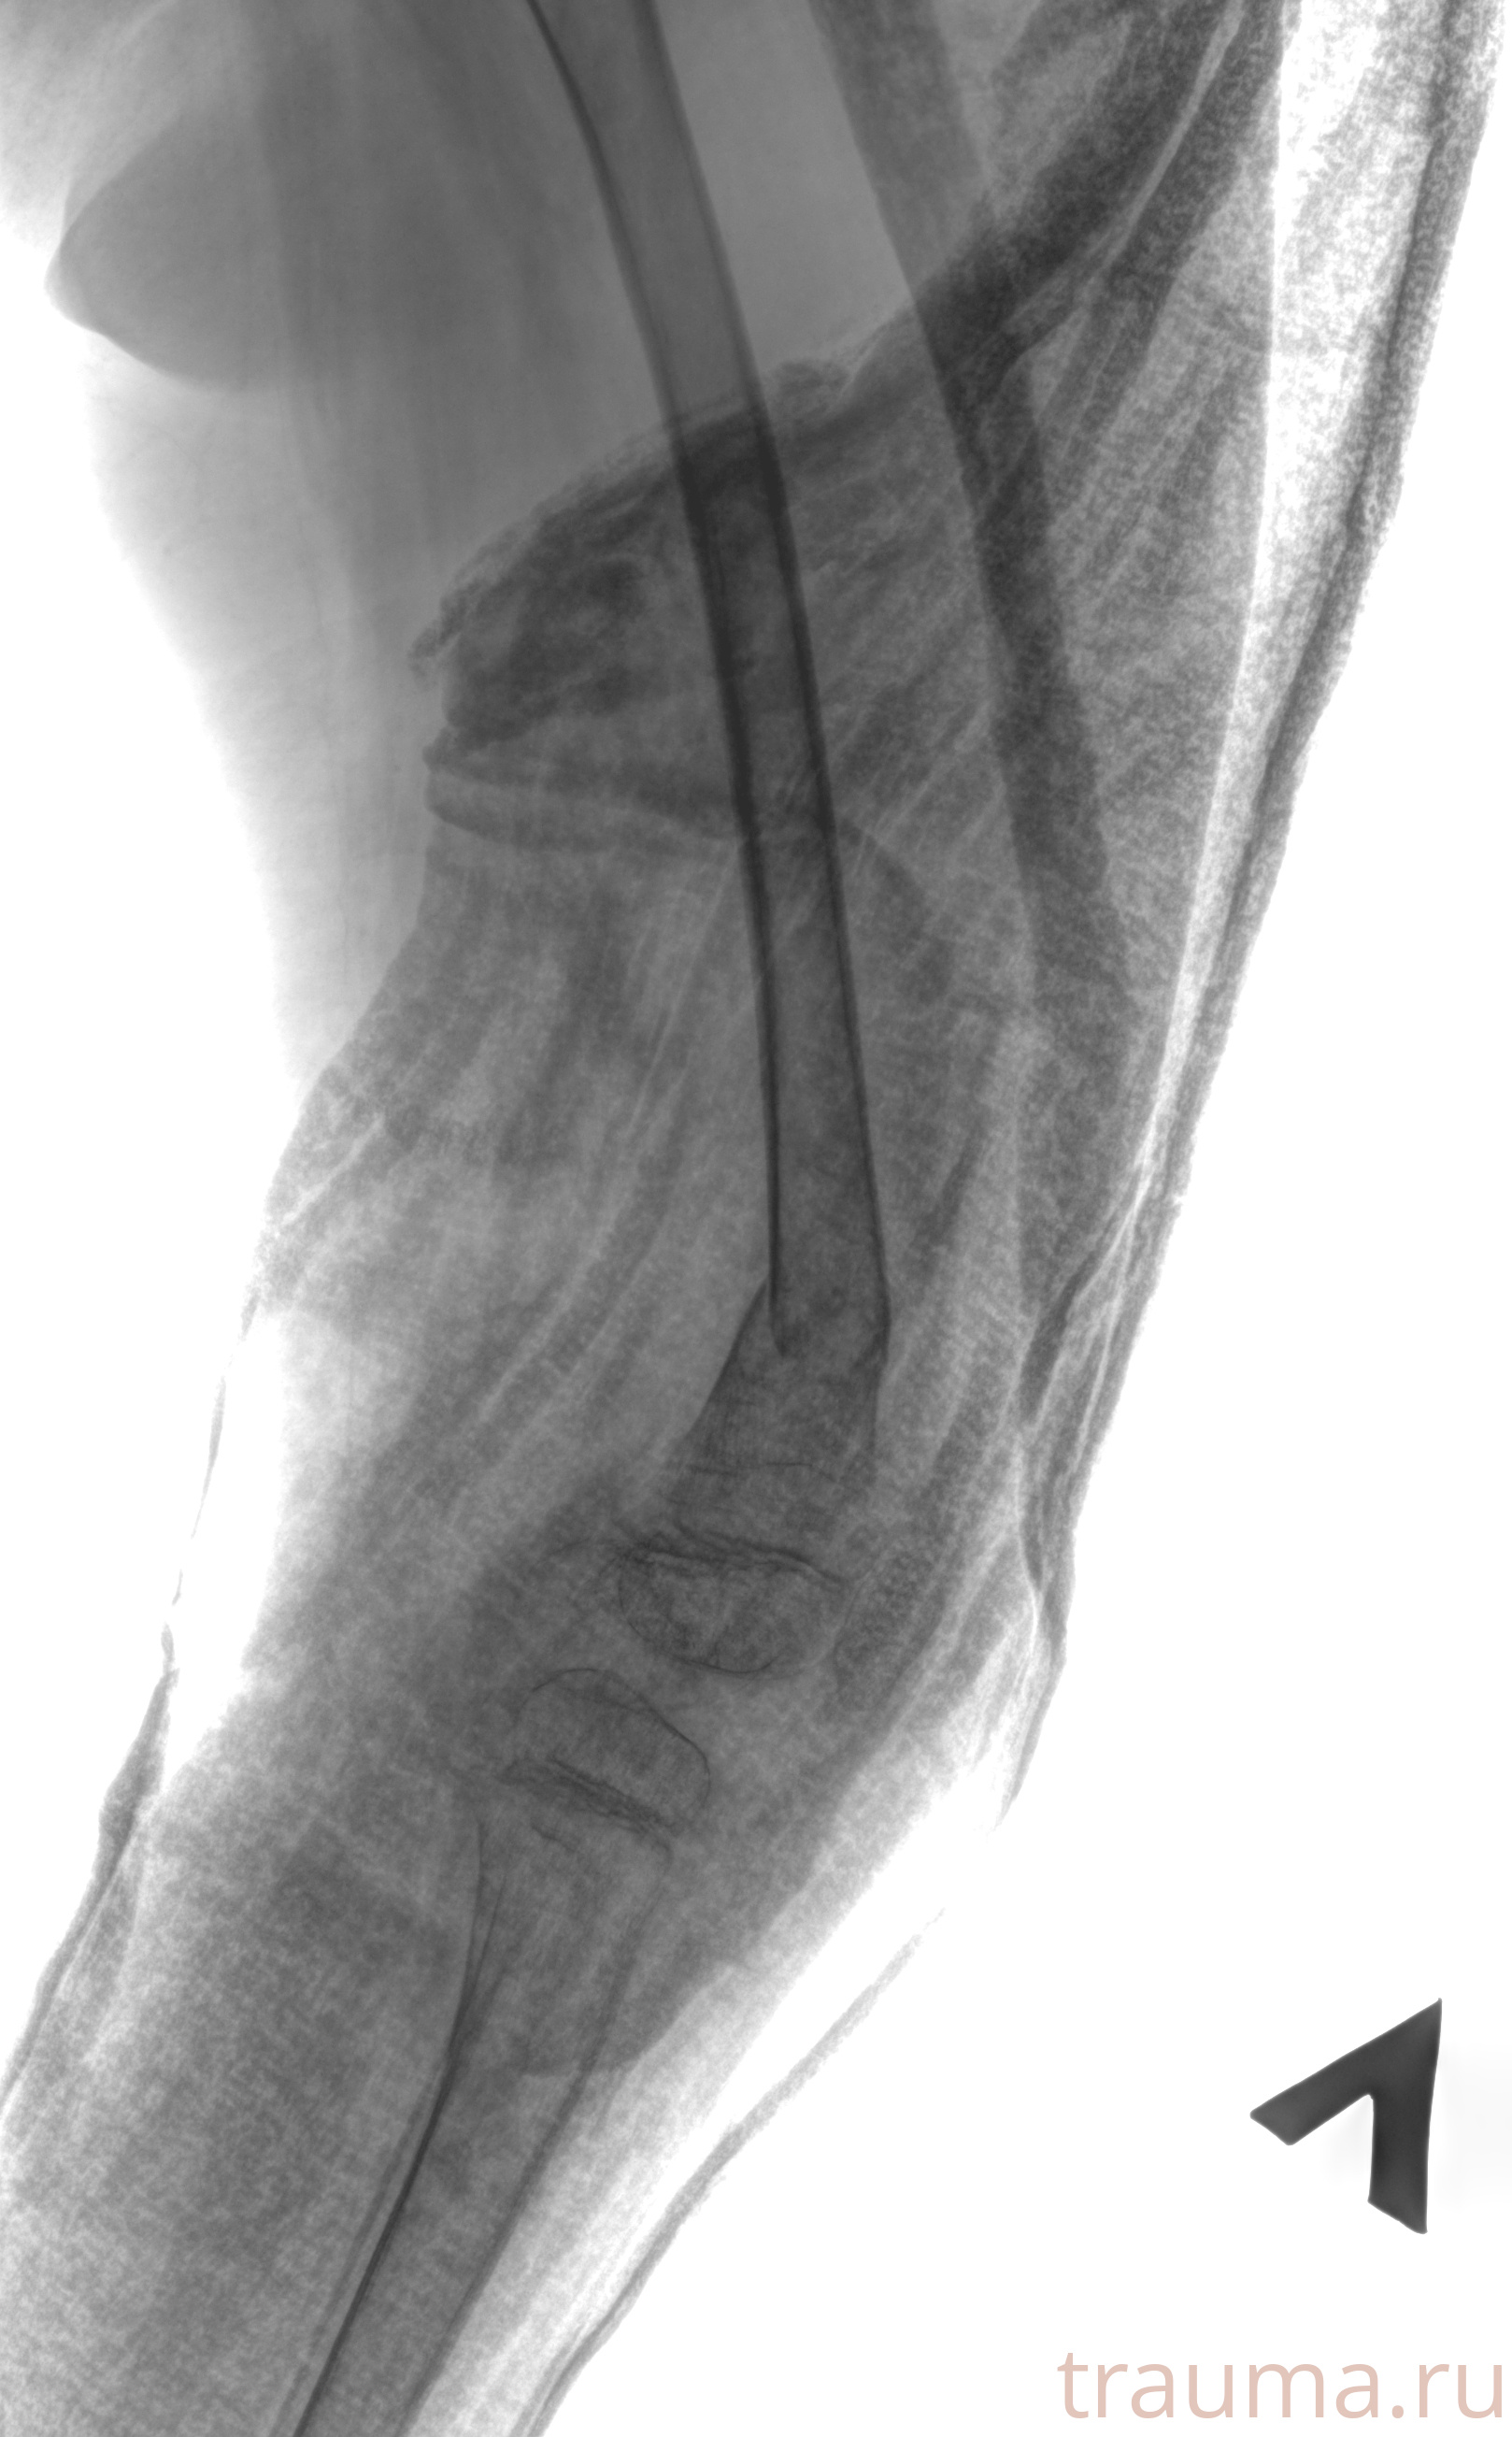

Рентгенограммы

Рентген на дому: по вашему адресу приезжает врач-рентгенолог, травматолог-ортопед с мобильным рентгеновским аппаратом, проводит диагностику травмы или заболевания, делает необходимые рентгенограммы, дает рекомендации по дальнейшему лечению. Получить качественные снимки в домашних условиях возможно благодаря уникальной методике, разработанной МосРентген Центром для института  Склифосовского